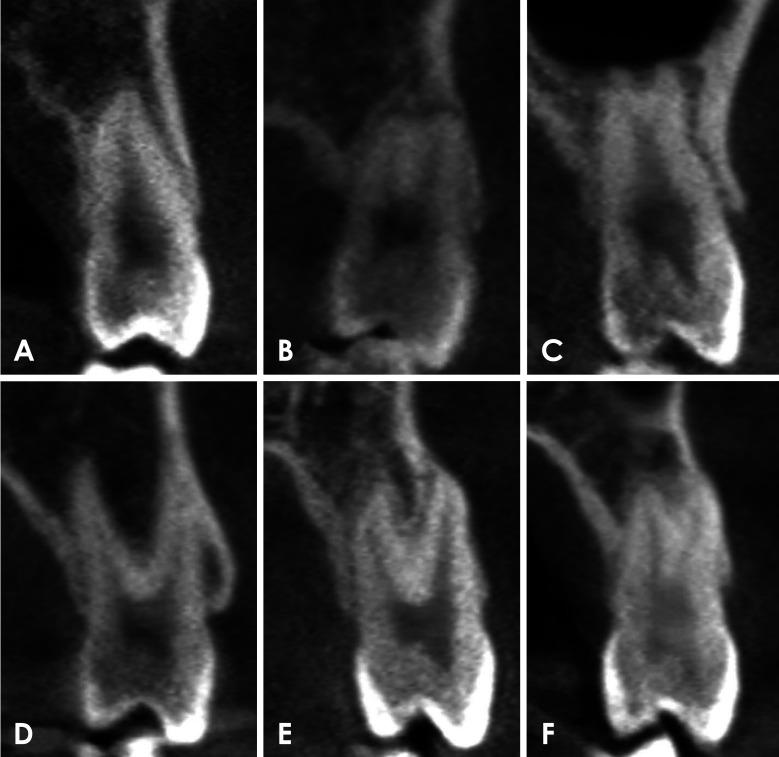

CBCT images of 585 maxillary first premolars and 578 maxillary second premolars from 303 patients were retrospectively reviewed. The number of roots was classified based on root morphology, and canal configurations were categorized into 8 types according to the Vertucci classification. For statistical analysis, chi-square or Fisher exact tests were employed to compare root number and canal morphology according to sex and tooth type.

CBCT analysis revealed that 71.5% of maxillary first premolars and 97.6% of maxillary second premolars had 1 root. The most common canal configuration in maxillary first premolars was Vertucci type IV (42.6%), whereas type I predominated in maxillary second premolars (76.5%). Significant differences in root number and canal configurations were found between men and women (<0.05), with single roots and Vertucci type I canals more commonly observed in women.

回顾性分析了303例患者的585颗上颌第一前磨牙和578颗上颌第二前磨牙的CBCT图像。根据牙根形态对牙根数量进行分类,并根据韦尔图奇分类法将根管形态分为8种类型。为进行统计分析,采用卡方检验或费舍尔精确检验来比较不同性别和牙齿类型的牙根数量及根管形态。

CBCT分析显示,71.5%的上颌第一前磨牙和97.6%的上颌第二前磨牙有1个牙根。上颌第一前磨牙最常见的根管形态是韦尔图奇IV型(占42.6%),而上颌第二前磨牙中I型占主导(占76.5%)。男性和女性在牙根数量和根管形态上存在显著差异(<0.05),女性中单根和韦尔图奇I型根管更为常见。